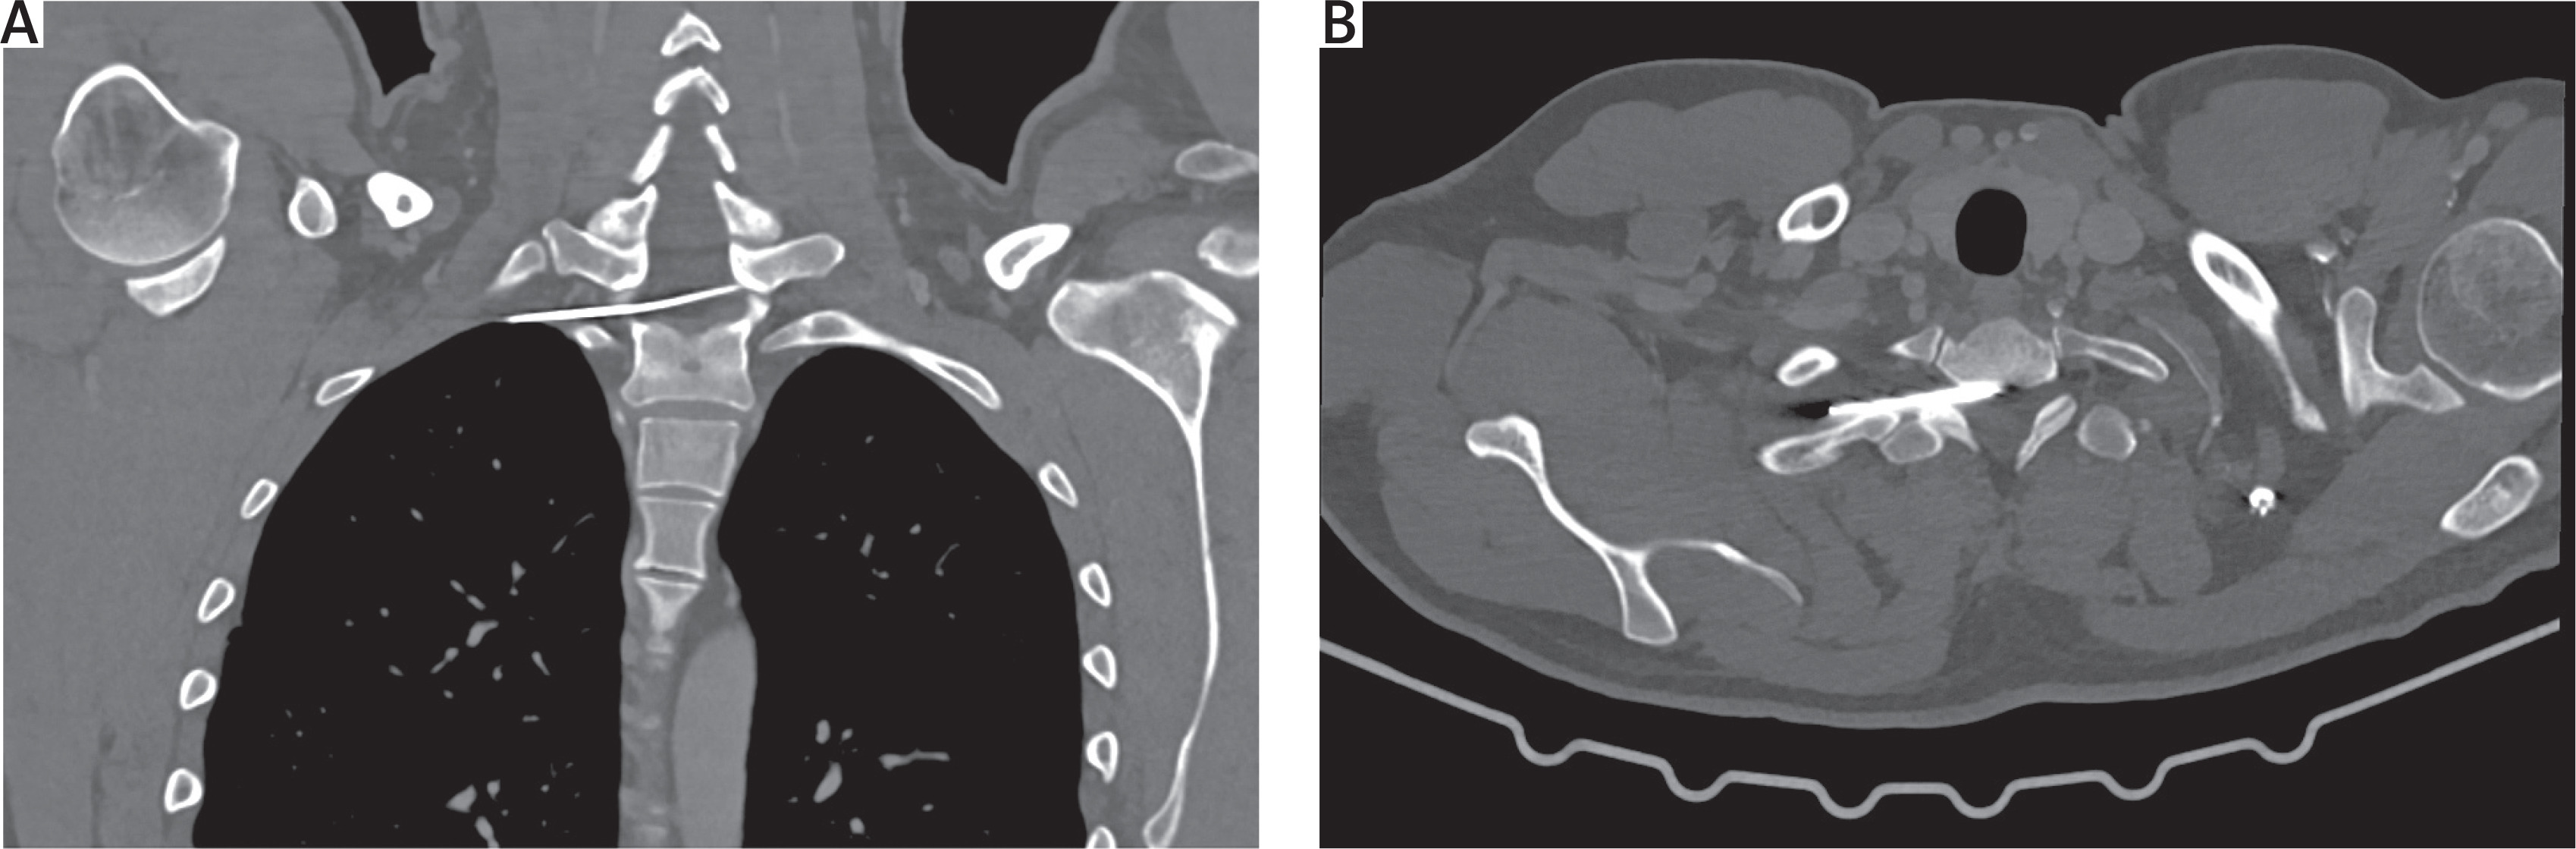

On radiological evaluation on chest X-ray a broken K-wire was observed with the distal part in the clavicle and the proximal part migrated into the thorax (Figure 1). Computed tomography revealed that part of the broken wire lay transversely across the spinal canal at the level of Th1. The length of this part was 7.0 cm, with the tip in the right mediastinum, posterior to the superior vena cava (Figures 2 A, B).